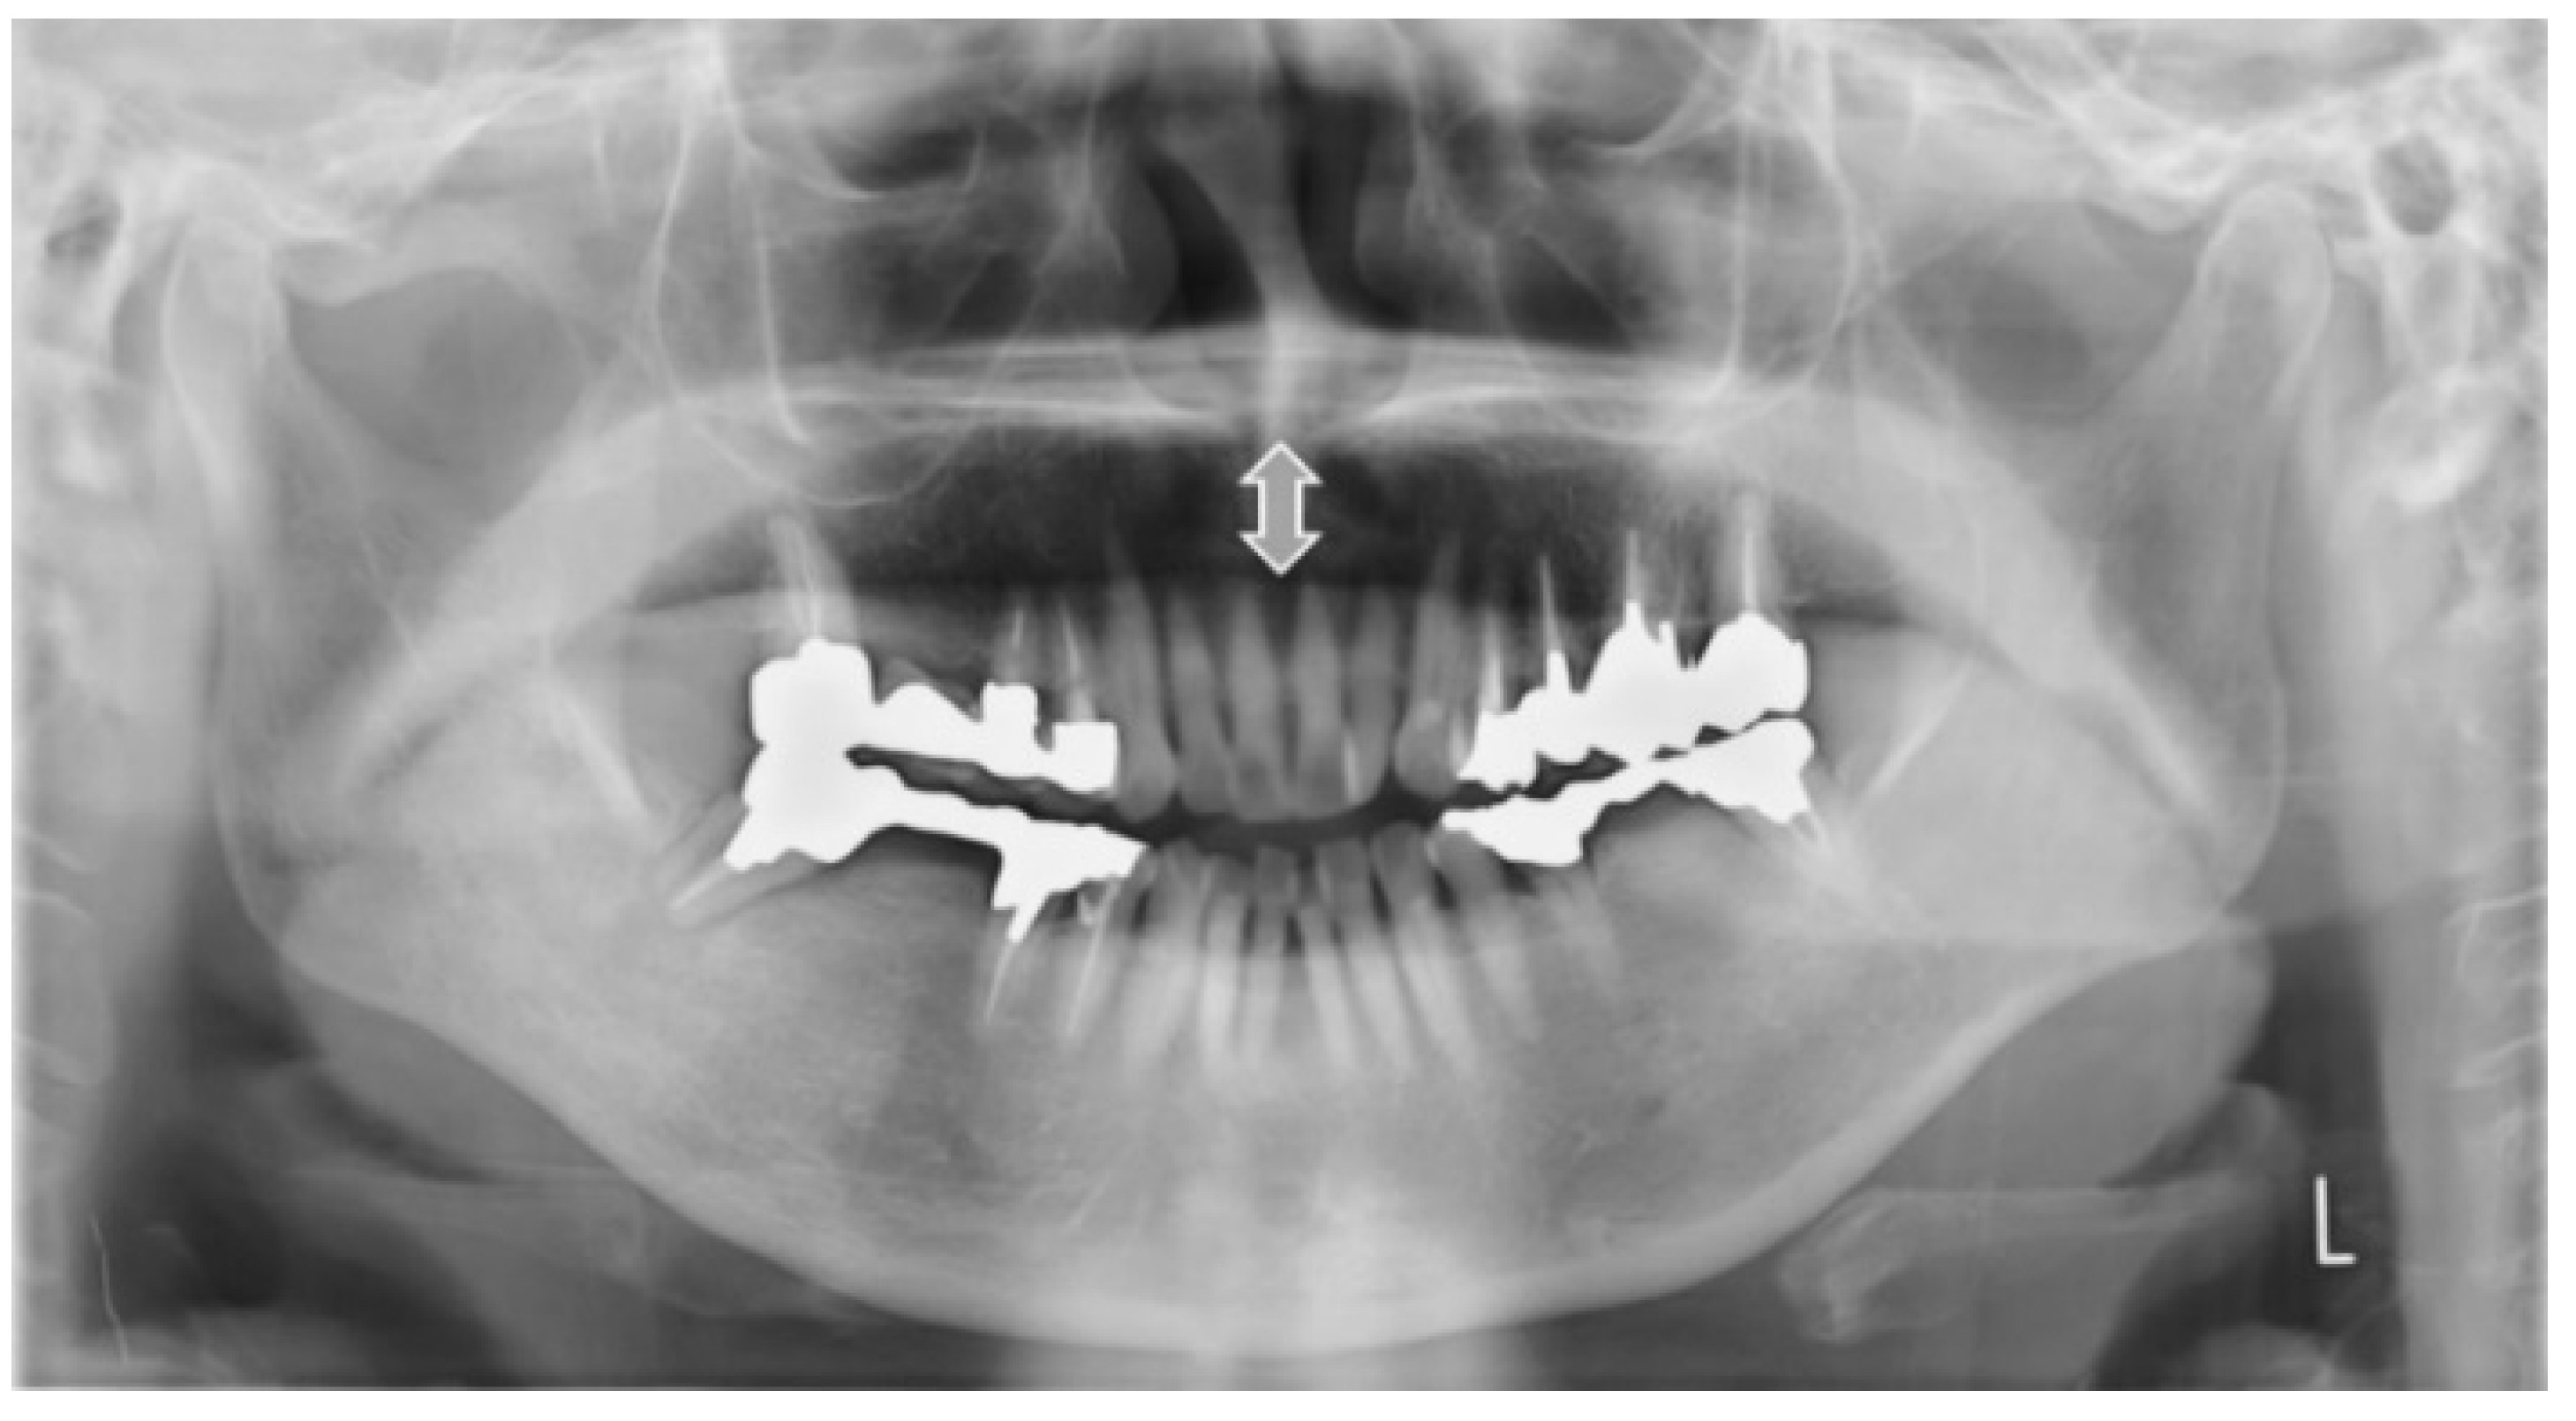

2.4.3. Measurement from the Tongue to the Palate on the Midline (mm)